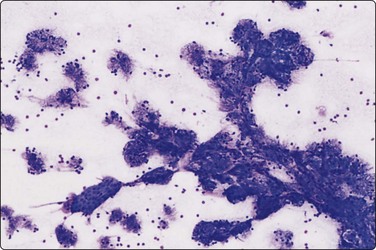

image image image image

Fig. 4.2 Cystically degenerate metastasis of well-differentiated squamous carcinoma

(A, B) Exfoliating atypical cells of ‘parakeratotic’ type in FNB smear and corresponding tissue section; (C, D) Other example with predominance of anucleate keratinized cells and clumps of keratin in the cyst lumen.

The diagnostic difficulties are due to the fact that squamous epithelial cells aspirated from a cystic metastasis of well-differentiated SCC are often anucleate or of parakeratotic type with a mature cytoplasm and a small pyknotic nucleus appearing cytologically bland, while inflammation of a benign cyst can result in immature squamous metaplasia and worrying cytological atypia. Figures 4.1 and 4.2 compare cells exfoliating from the lining of inflamed branchial cysts with those from cystic SCCs seen in histological sections. Helpful clues are that material sampled from a cystic SCC is more obviously necrotic than inflammatory, and a careful search usually reveals a few squamous epithelial cells with malignant nuclear features or abnormal keratinised cells with bizarre, globoid shapes and dense orangeophilic (Pap) cytoplasm. The nuclear atypia and hyperchromasia seen in squamous cells from a benign cyst is of degenerative type. But the distinction is not always easy (see Figs 4.1C and D). In some cases, the FNB can only be reported as indeterminate. The only ancillary test we have found useful in this setting is HPV DNA sequencing. Occult tonsillar carcinomas and other oral cavity carcinomas with cystic lymph node metastases are a common clinical problem. Many such carcinomas contain HPV DNA as evaluated by PCR or other molecular testing and a positive result in an FNA sample is strong evidence that a lesion is metastatic carcinoma rather than a branchial cleft cyst or other benign cyst.